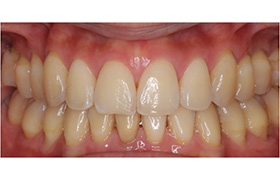

Before

After

再生療法

(歯周組織再生療法)

歯周病などにより、顎骨や歯根膜を失った際の治療法です。エムドゲインは哺乳類由来のタンパク質で、歯の発生を促す作用があります。骨を失った箇所にエムドゲインを塗布することで、造骨細胞などの歯の周辺を形作る細胞群が活性化されて、顎骨およびその周辺組織が再生されます。